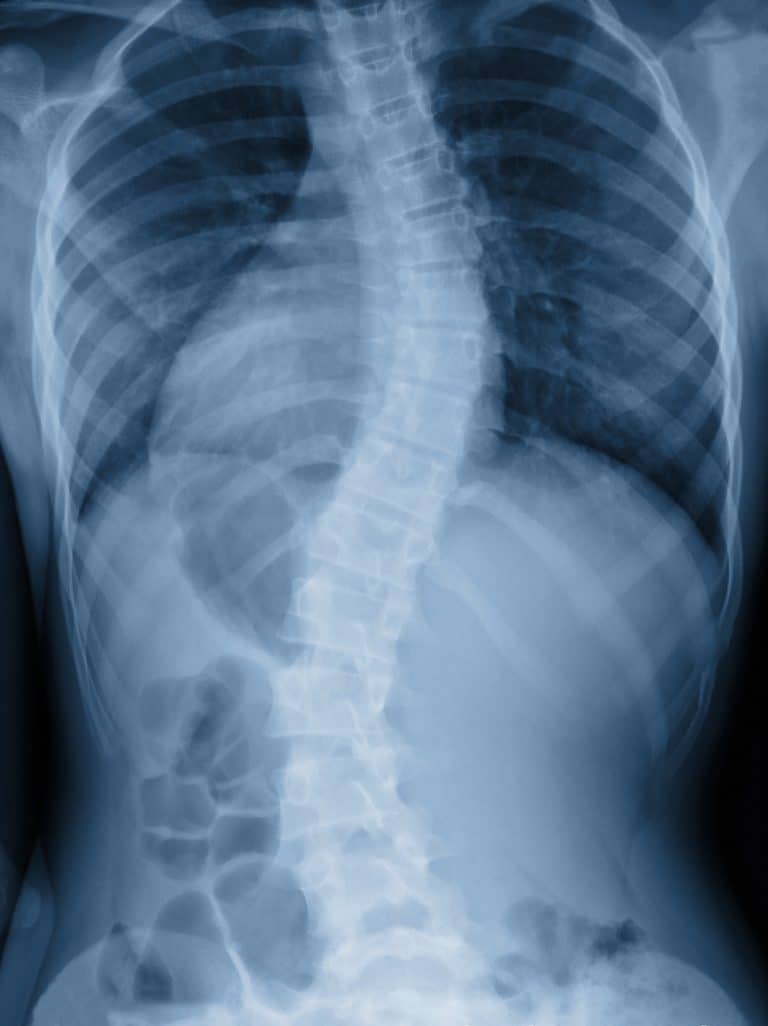

X-ray image of adult patient with severe spine curvature

The spine forms a natural S-shaped curve that can be seen when looked at from the side. This curvature, which is called lordosis, allows for an even distribution of weight and flexibility of movement. Scoliosis refers to any abnormal curvature or a curve of more than 10 degrees. When the spine abnormality develops after complete skeletal growth, itโ€™s considered adult scoliosis. Adult scoliosis research suggests that one in every three adults between the ages of 40 and 90 may be living with scoliosis and not know it.